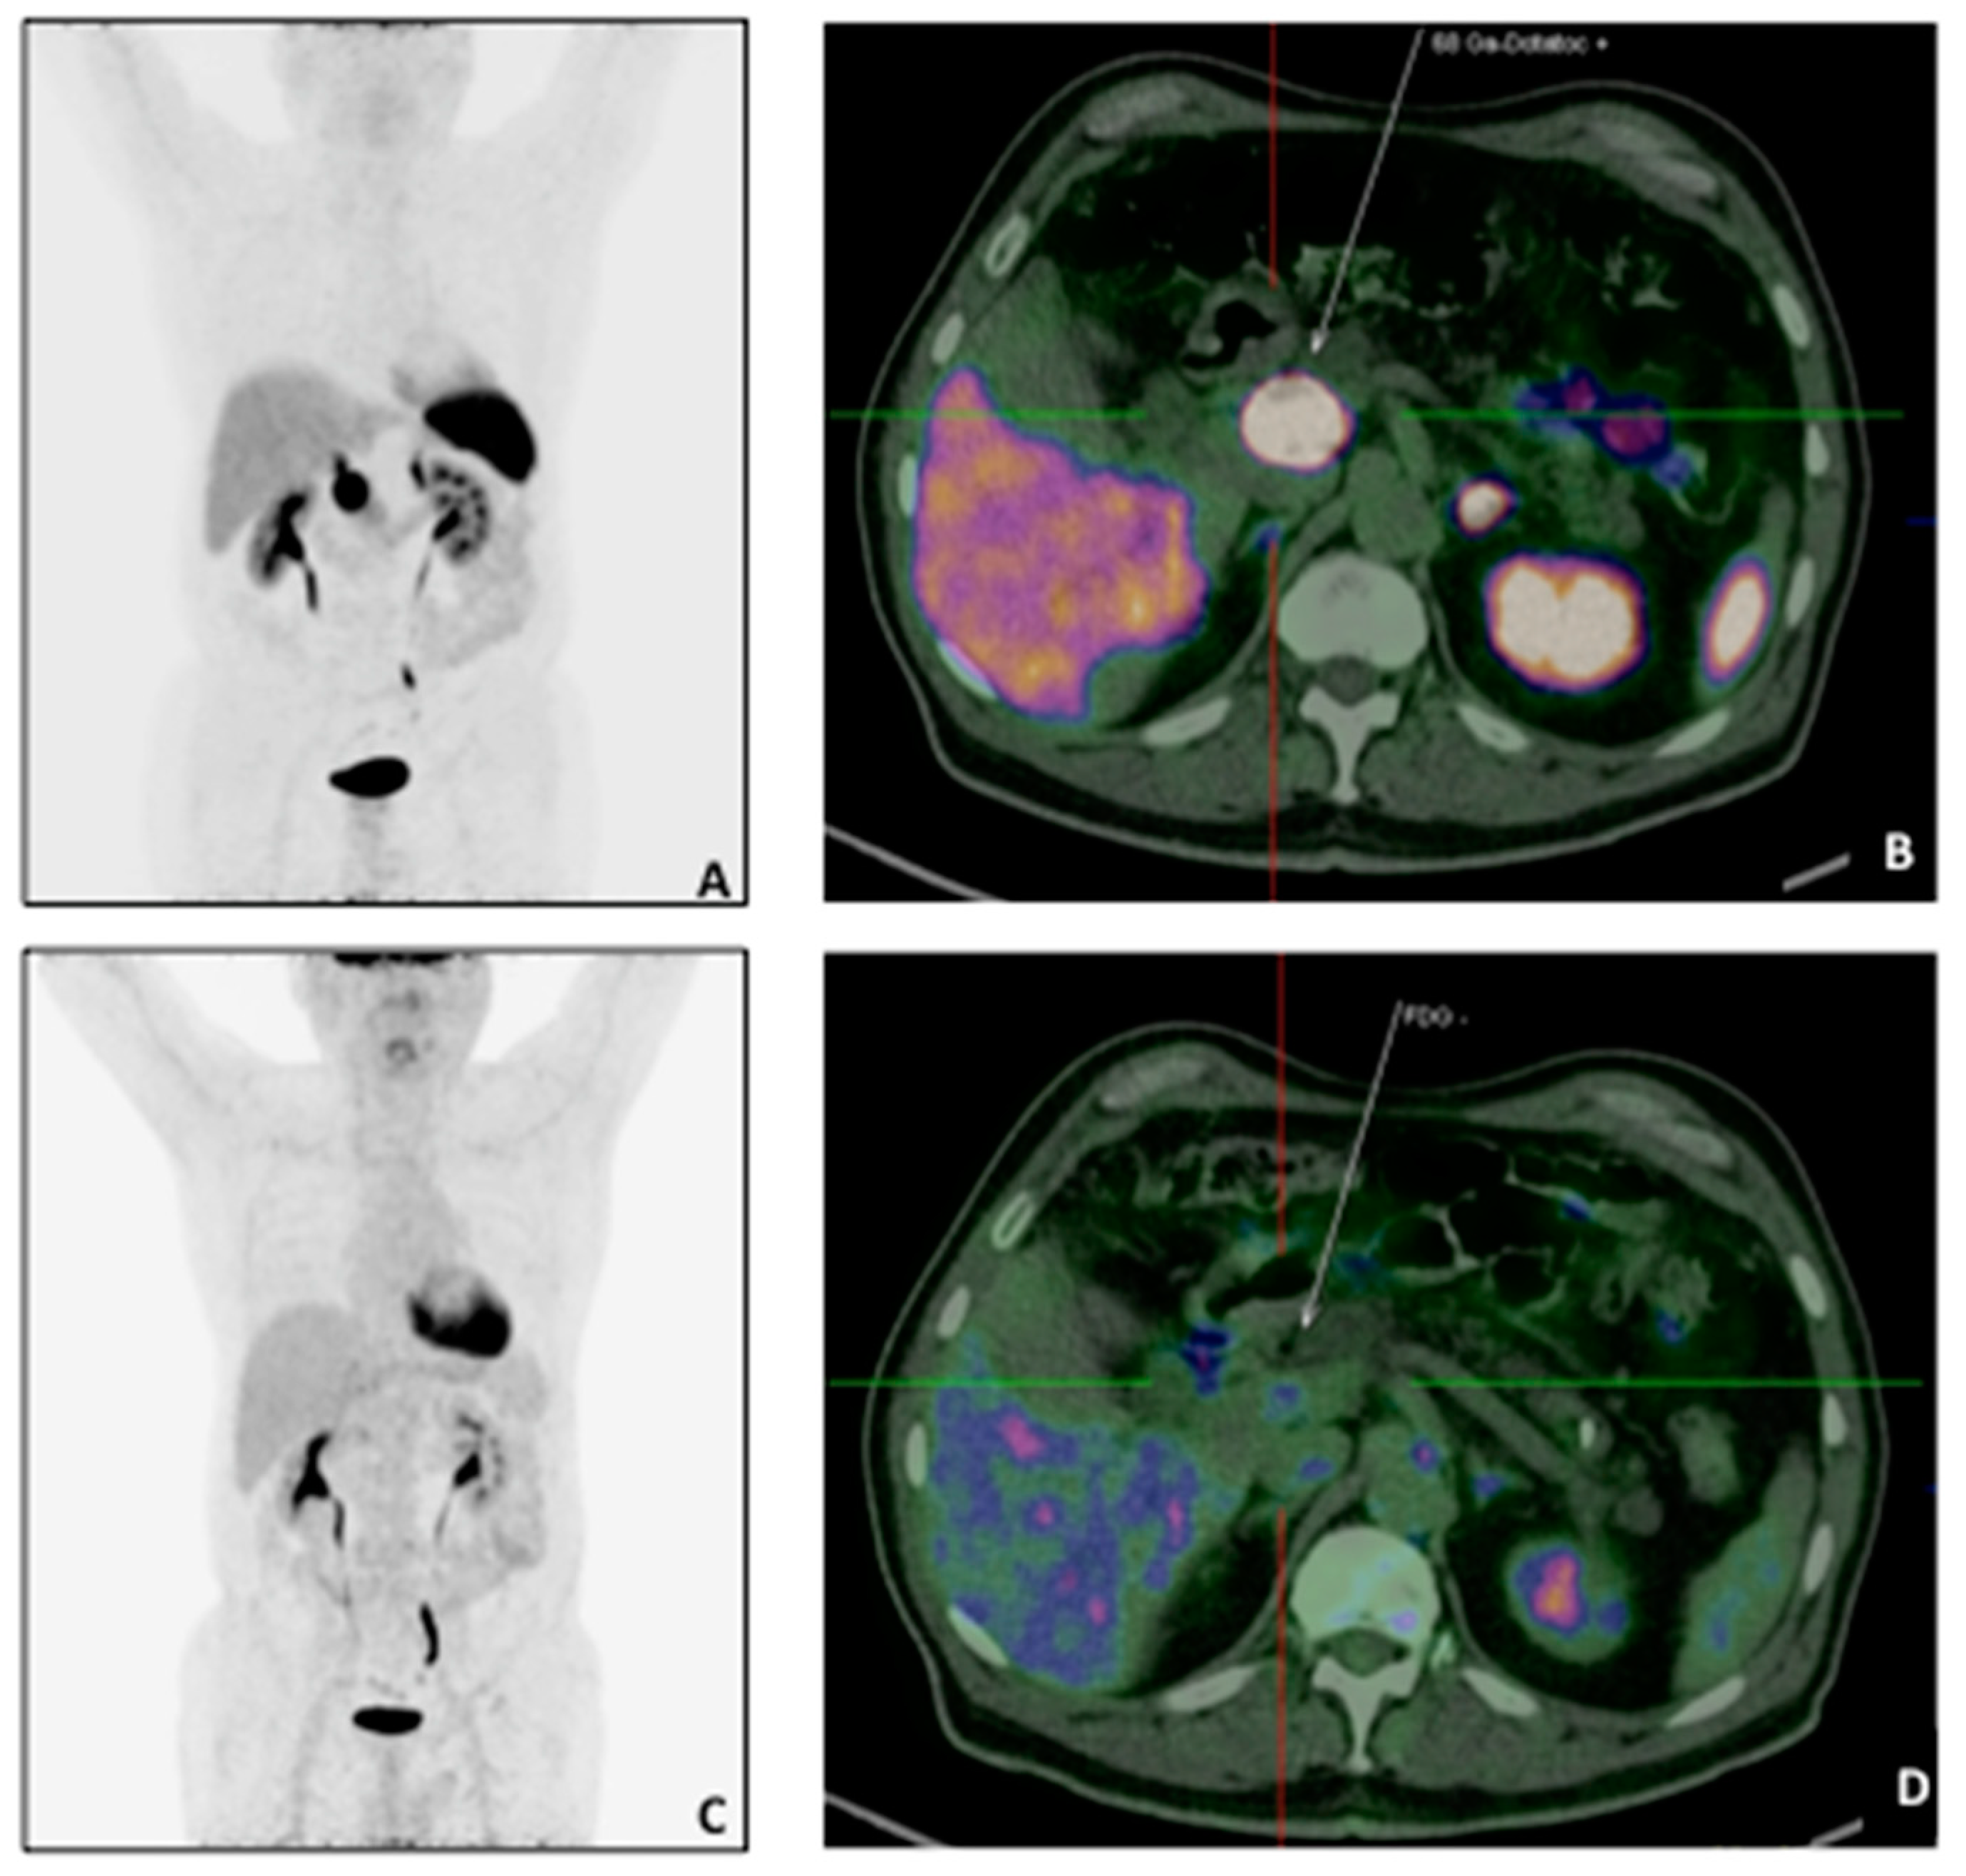

Among the 22 patients with a negative scan 12/22 (54.5%) had G1 (Ki67: 0.6% in 1/12, 1% in 10/12, 2% in 1/12) and 10/22 (45.4%) with G2 (Ki67: 3% in 1/10; 4% in 1/10, 5% in 3/10, 10% in 2/10, 17% in 1/10, 18% in 1/10, and 20% in 1/10) (Figure 1).

Figure 1.

A 73 years-old patient with pancreatic NET (G2, pT2N1M0) underwent 68Ga-DOTATATE and 18F-FDG PET/CT for staging purpose. The68Ga-DOTATATE MIP (A) and transaxial sections (B) showed intense uptake in correspondence of the primary tumour (white arrow: SUVmax: 107.1) with a negative 18F-FDG scan (MIP: (C); transaxial: (D).